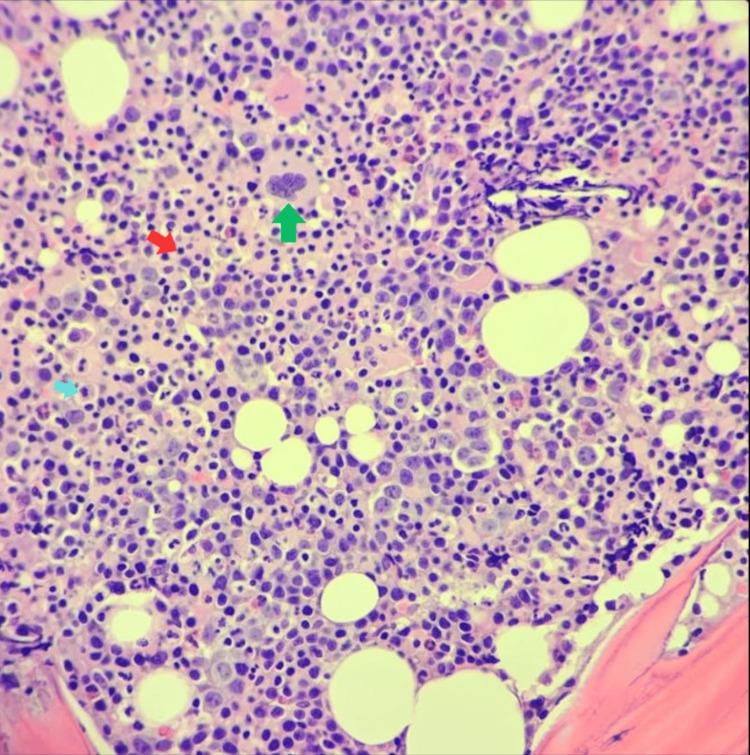

Thrombopoietin (THPO) is a regulator of megakaryopoiesis and thrombopoiesis. Mutation of the gene is known to cause congenital amegakaryocytic thrombocytopenia (CAMT2), which is a rare inherited disorder characterized by early infancy thrombocytopenia and absent or decreased megakaryocytes with gradual progression to pancytopenia. We report the case of a Saudi girl who had been asymptomatic until age seven when she was found to have unexplained thrombocytopenia. Whole-genome sequencing detected loss between the genomic coordinates (chr3:184088108-184090520) partially encompassing exon 6 of the gene in a homozygous state, which is reported as a new variant. This report highlights the importance of genetic testing for unexplained persistent hematological abnormalities for early diagnosis, especially in consanguineous populations.

血小板生成素(THPO)是巨核细胞生成和血小板生成的调节因子。已知该基因突变会导致先天性无巨核细胞血小板减少症(CAMT2),这是一种罕见的遗传性疾病,其特征为婴儿早期血小板减少,巨核细胞缺失或减少,并逐渐发展为全血细胞减少。我们报告了一名沙特女孩的病例,她在7岁之前一直无症状,之后被发现患有不明原因的血小板减少症。全基因组测序检测到在基因组坐标(chr3:184088108 - 184090520)之间存在缺失,该区域部分包含该基因的外显子6,呈纯合状态,这被报告为一种新的变异。本报告强调了对不明原因的持续性血液学异常进行基因检测以早期诊断的重要性,尤其是在近亲结婚人群中。